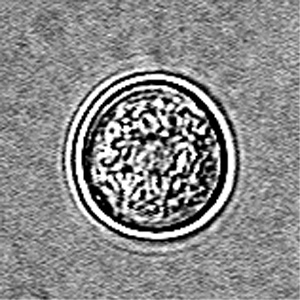

Acanthamoeba spp.

CYST